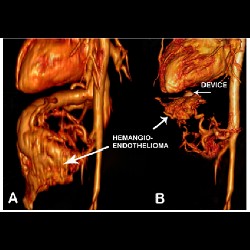

Transcatheter Intervention for Infantile Hepatic Hemangioendothelioma with Amplatzer Duct Occluder II

Transcatheter Intervention for Infantile Hepatic Hemangioendothelioma with Amplatzer Duct Occluder II

Transcatheter Intervention for Infantile Hepatic Hemangioendothelioma with Amplatzer Duct Occluder II

Transcatheter Intervention for Infantile Hepatic Hemangioendothelioma with Amplatzer Duct Occluder II